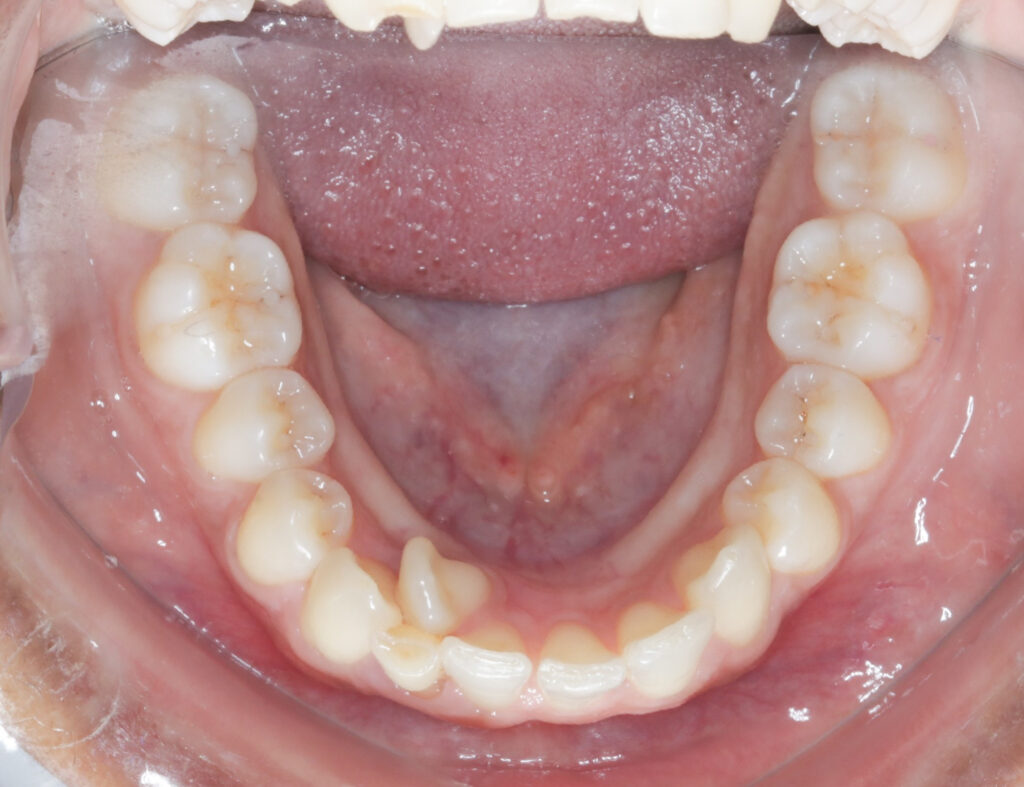

- Crowded or Misplaced Teeth — If the teeth are blocked out, overlapped, or misplaced, it could indicate a lack of space for permanent teeth.